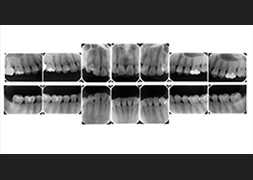

歯周病になってしまった原因と進行状況を調べます。詳しい問診、レントゲン(パノラマX線写真・全顎デンタルX線写真)、歯周ポケットの深さを測定する歯周組織検査、スタディモデル(歯型)、口腔内写真、歯周ポケットから採取したプラークをDNAレベルで検査する歯周病細菌検査、からなります。

※進行状況に応じて必要な検査を行います。

-

パノラマX線写真

-

全顎デンタルX線

写真 -